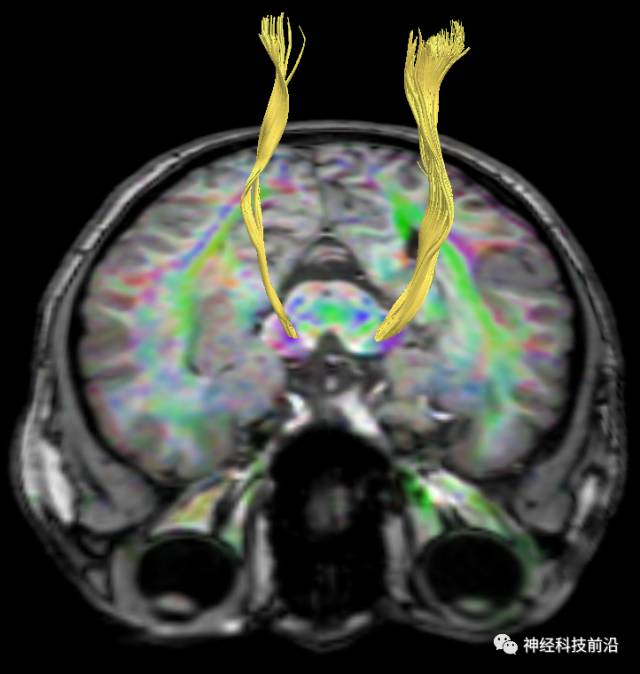

上述纤维束与小脑中脚的位置毗邻

终上所述:脑干高信号为一近环形纤维束,内囊后肢高信号为皮质脑桥束,皮质脊髓束在中脑位置略靠后。高信号位于中脑前缘,是皮质脑桥束的位置所在,另外有部分桥连纤维。